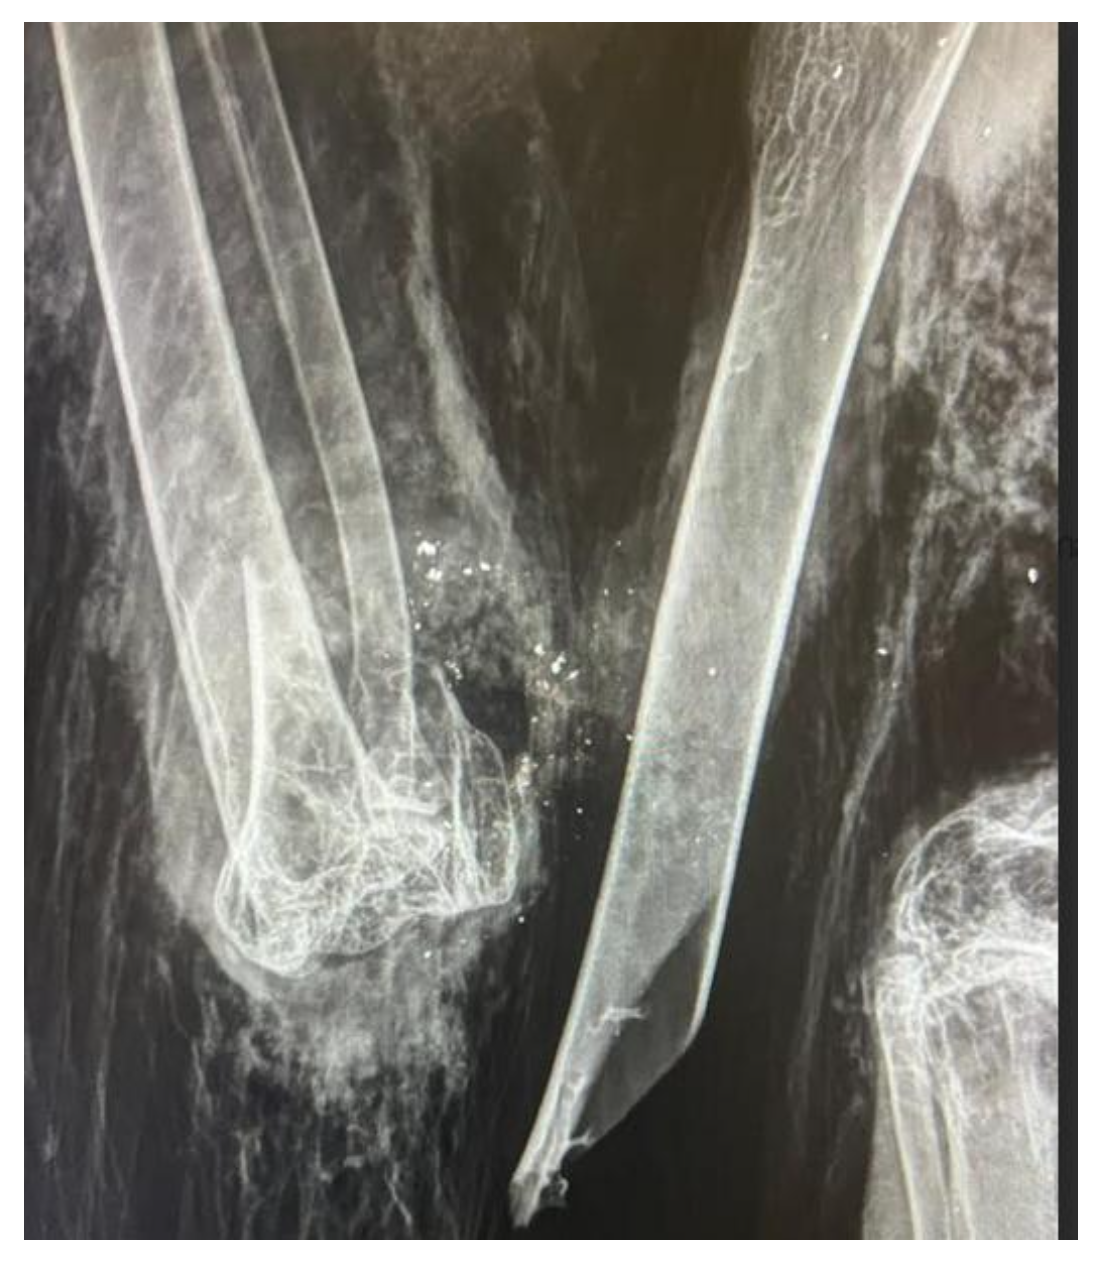

Il présentait une fracture ouverte de l’humérus droit, avec la présence de fragments métalliques, très probablement provoqués par le tir d’une munition de gros calibre.

Radiographie d’admission : fracture ouverte de l’humérus droit associée à la présence de fragments métalliques dans le foyer de fracture.